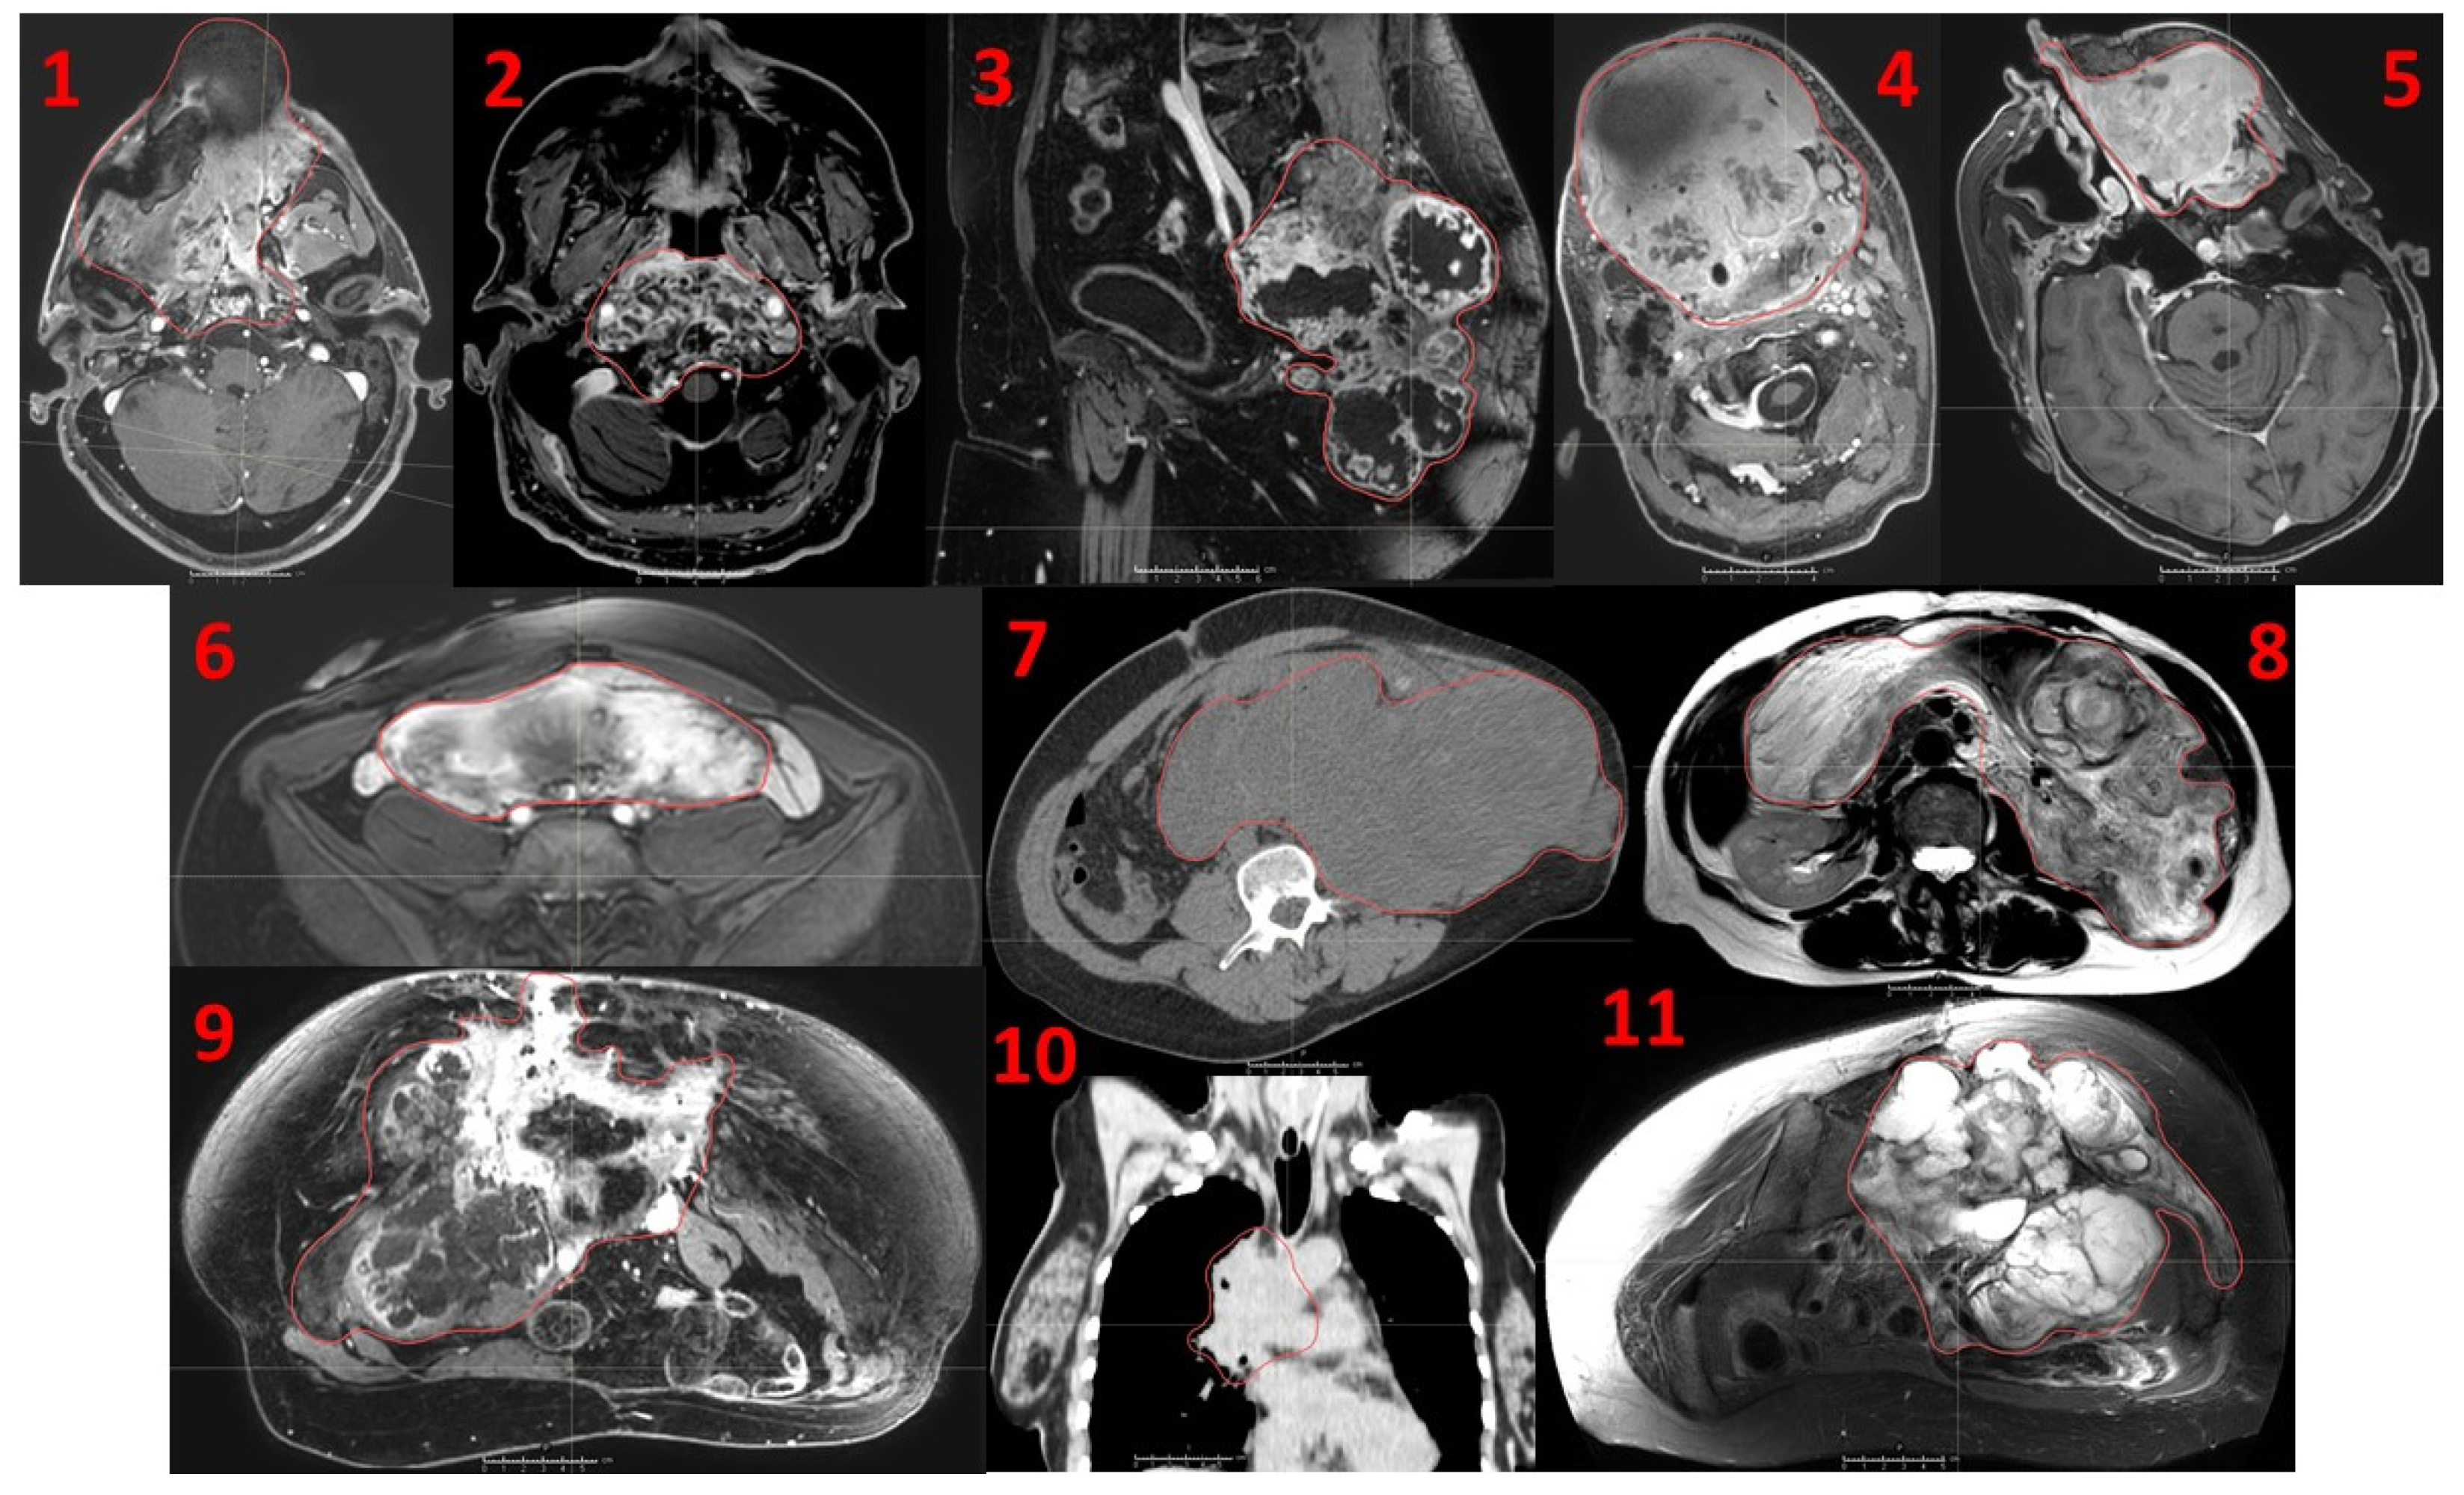

Figure 1. Eleven consecutive patients affected by recurrent unresectable bulky tumors treated with a novel Particle-PATHY approach: 1. Leiomyosarcoma, 2. Skull base chordoma, 3. Sacral chordoma, 4. Squamous-cell carcinoma of oral cavity, 5. Adenocarcinoma of nasal cavity, 6. Intraperitoneal soft-tissue sarcoma, 7. Intraperitoneal non-seminomatous germ-cell carcinoma, 8. Intraperitoneal liposarcoma, 9. Pelvic chondrosarcoma, 10. Squamous-cell lung carcinoma, 11. Pelvic chondrosarcoma. Red contours indicate the Gross Tumor Volume (GTV).

We conducted a retrospective review approved by the local ethic committee to assess the impact of Particle-PATHY on Quality of Life (QoL), tumor downsizing (neoadjuvant effect), tumor control and survival among patients affected by recurrent unresectable bulky tumors unsuitable for conventional radio-chemotherapy. This series includes the first eleven consecutive patients treated at our institution from March 2020 until December 2021 that were previously subjected to BSC and who were referred for Particle Therapy but considered unsuitable for conventional Particle Therapy by our New Patient Review Board (Figure 1).

Patient and disease characteristics are summarized in Table 1 and Table 2. There were seven men (64%) and four women (36%). The average patient age was 56 years (range 25–78). Most of the patients were in poor general conditions, the median KPS was 60% with >50% of the patients´ KPS as low as 30–60%. All patients had typically large, symptomatic, recurrent bulky tumors (stage rcT4) that, due to the very high volumes and intimate relationship with nearby critical structures, did not have any treatment option including conventional radiotherapy or particle therapy. They were all pretreated per standard of care treatments, including systemic therapy, surgery, and radiotherapy resulting subsequently in progressive disease (PD). Particularly, five patients (45%) had prior photon radiotherapy at the local site, two of whom already received re-irradiation before Particle-PATHY. The average previous radiation dose was 82.4 Gy (range 60–120). Five patients (45%) had been administered chemotherapy, biologic, or immunotherapy without response. Ten out of eleven patients (91%) had previously undergone surgery, of which eight (73%) were treated with multiple surgeries. Only two patients (18%) received subsequent immunotherapy due to PD following Particle-PATHY, without response. Five patients (45%) had advanced-regional (cN3) or distantly metastatic (cM1) disease allowing assessment for abscopal effect. All patients had significant tumor-related symptoms that were uncontrolled prior to treatment. Seven out of eleven (63%) patients had sarcoma.

Treatment characteristics are summarized in Table 3. Irradiated bulky-tumor sites were skull base (18%), head and neck (18%), lung (9%), abdomen (27%) and pelvis (27%). All three treated abdominal lesions were intraperitoneal. Mean tumor diameter and volume were 15.6 cm (range 6–27.5) and 1460 cc (range 76–5645.9), respectively. The mean volume of targeted BTV was 431.7 cc (range 36.1–1494) representing on average 29.6% of the mean GTV volume; i.e., approximately 1/3 of the GTV was targeted. Six patients (54%) were treated with 10 or 12 Gy delivered three times on consecutive days to the single BTV volume (BTV1). However, in the remaining five patients (46%) affected by particularly large tumors the dose corresponding to 10 and 12 Gy or 12 and 15 Gy was delivered three times to two tumor sub-volumes (BTV1 and BTV2), respectively (Figure 2 and Figure 3). Seven patients (64%) were treated with mixed proton and carbon ion therapy while four of them either with full proton (18%) or carbon ion (18%) therapy. The “immune-dose” in terms of the PIM-sparing was as low as it was initially intended: the total average mean dose was 5.8 Gy, D50 ≤ 2.8 Gy, D30 ≤ 0.7 Gy and D20 ≤ 0.2 Gy in three fractions.